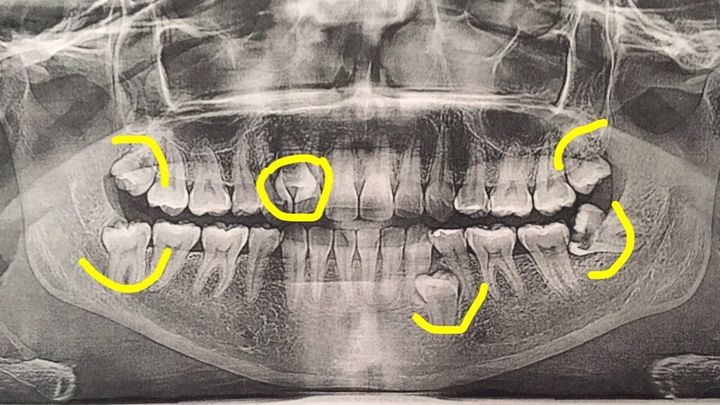

I have 4 wisdom teeth coming, one of them coming in completely sideways that now has a hole in it, and is close to hitting my jaw bone that needs to be out urgently. It has been causing pain, fogginess, and migraines.

In addition to that, I have 2 extra (supenumerary) teeth, one that is already out, and the other on the same side as the impacted wisdom tooth, creating pain and discomfort as well.